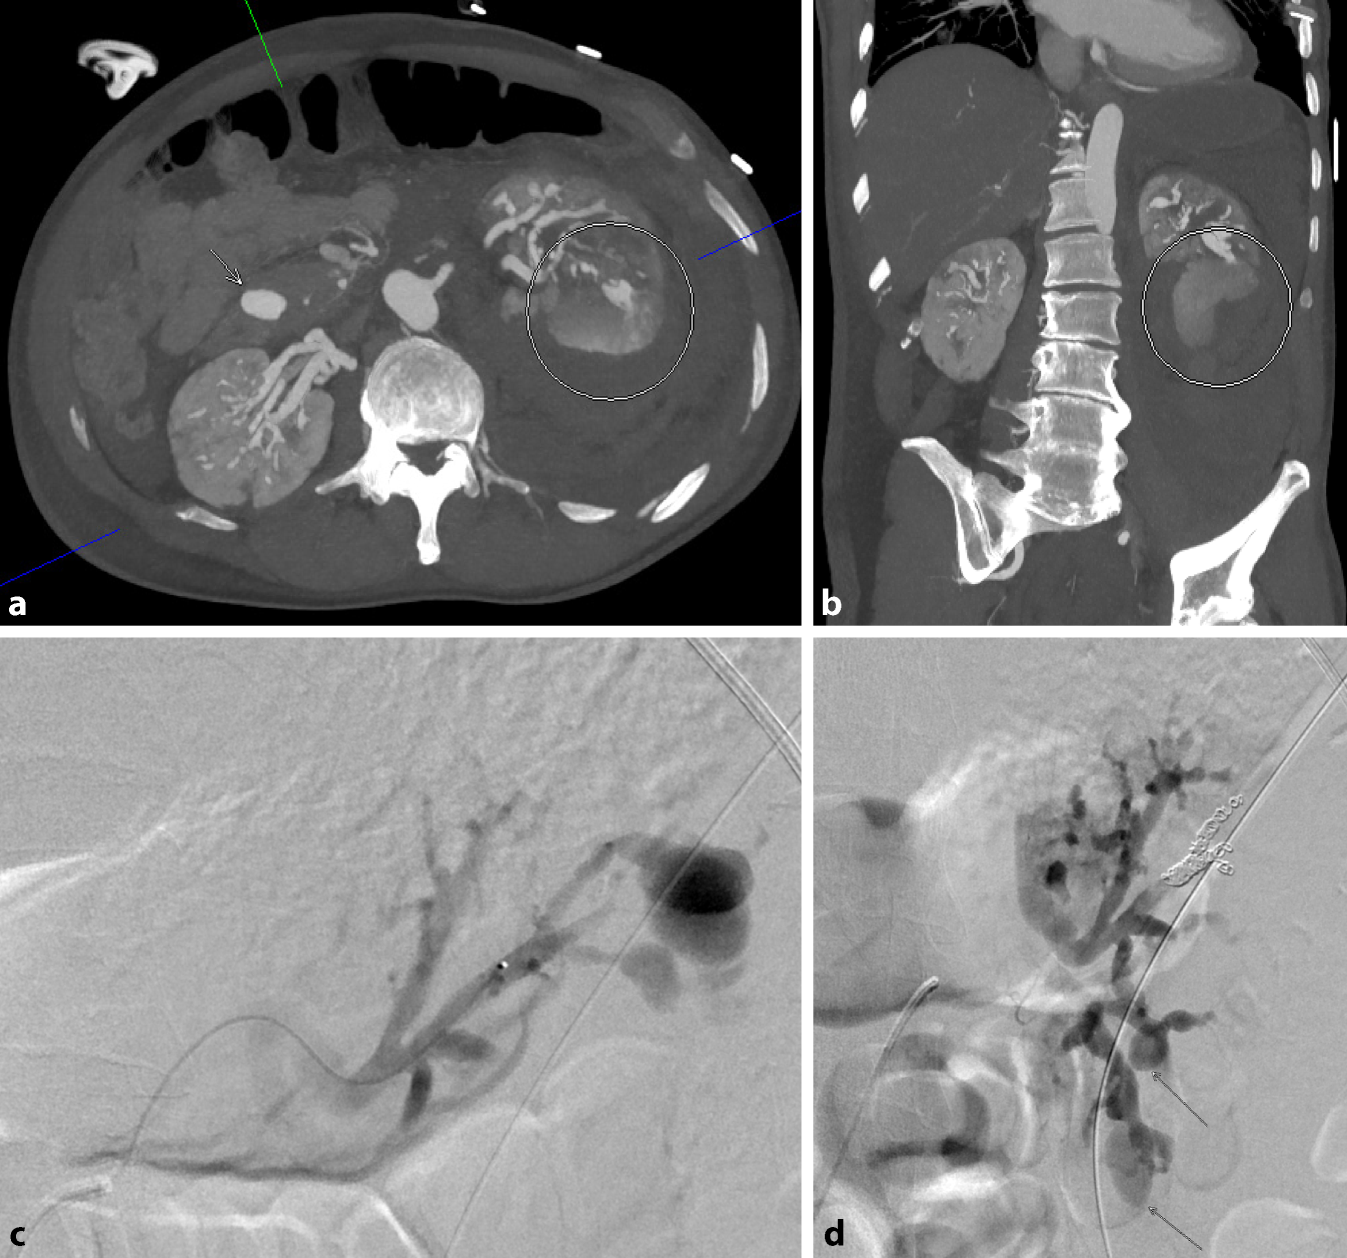

In der Histologie der Lungen- und Lymphknotenbiopsie wurden keine Neoplasien, Granulome oder Hinweise auf eine Castleman-Erkrankung beobachtet, die Befunde waren passend für eine organisierenden Pneumonie. Drei Wochen nach Beginn des Fiebers entwickelte der Patient plötzlich starke Bauchschmerzen, mit klinisch bretthartem Abdomen ohne äußere Blutungsstigmata mit Zeichen eines hämorrhagischen Schocks bei Blutdruckabfall auf systolisch 45 mm Hg, Tachykardie, kalte Peripherie und Anämie (Hb 50 g/l). Eine notfallmäßig durchgeführte abdominale CT-Untersuchung ergab eine perakute abdominale Blutung aus der linken Niere, die sich in das Retroperitoneum und in die Beckenregion ausbreitete (Abb. 2). Zudem wurde ein Verschluss der Arteria lienalis mit nahezu aufgehobener Perfusion der Milz festgestellt und weitere multiple Aneurysmata der abdominalen Arterien (z. B. eines intrapankreatischen Arterienasts und entlang der pankreatikoduodenalen Arkade) im Sinne einer fulminanten generalisierten Arteriopathie. Die konventionelle Notfallangiographie zeigte neben den Aneurysmen der Nierenarterienäste auch mehrere perlschnurartige Gefäßkaliberirregularitäten. Ein rupturiertes Aneurysma/Pseudoaneurysma, das von einem Ast der linken inferioren Nierenarterie ausging, wurde als Ursache der Blutung identifiziert und mittels Coiling des aneurysmatragenden Nierenarterienasts ausgeschaltet. Die Blutung konnte so gestoppt werden (Abb. 2). In Zusammenschau der Befunde stellten wir die Diagnose einer Polyarteriitis nodosa mit einer Gefäßruptur, intraabdominellen Blutung und einem hämorrhagischen Schock. Therapeutisch wurde mit Methylprednisolon intravenös begonnen (500 mg/Tag über 6 Tage). Jedoch kam es bereits am 4. Tag zu einer erneuten arteriellen Blutung, die notfallmäßig mit einem Coiling eines peripheren Asts der A. colica dextra versorgt werden musste (Abb. 3). Angiographisch demarkierten sich weitere Aneurysmen und perlschnurartige Gefäßkaliberirregularitäten der abdominellen Arterien z. B. im Leber- und Nierenhilus links und in der pankreatikoduodenalen Arkade. Nach klinischer Stabilisierung erfolgte eine Umstellung auf Prednison 1 mg/kg Körpergewicht und zusätzlich der Beginn mit Cyclophosphamid. Hierunter wurde ein Rückgang des CRP und der BSR festgestellt. Der Patient erhielt insgesamt 12 (monatliche) Cyclophosphamid-Infusionen (Kumulativdosis 11,6 g), während Prednison auf 5 mg täglich reduziert wurde, was zu einer partiellen Remission der Polyarteriitis nodosa führte. Ein Mangel an Adenosin-Deaminase Typ 2 wurde nicht festgestellt. Danach wurde eine Behandlung mit Tocilizumab 8 mg/kg Körpergewicht intravenös alle 4 Wochen begonnen, die zu einer vollständigen Remission führte und das Absetzen von Prednison ermöglichte. Hierunter zeigte sich in der MRT-Angiographie ein vollständiges Verschwinden der Aneurysmata und Pseudoaneurysmata innerhalb der gastrointestinalen und renalen Arterien (Abb. 4).

Abb. 4

Abdominelle MIP einer MR-Angiographie in koronarer Schichtung: Die multiplen arteriellen abdominellen Aneurysmata sind nicht mehr identifizierbar; die perlschnurartigen Gefäßkaliberirregularitäten deutlich regredient